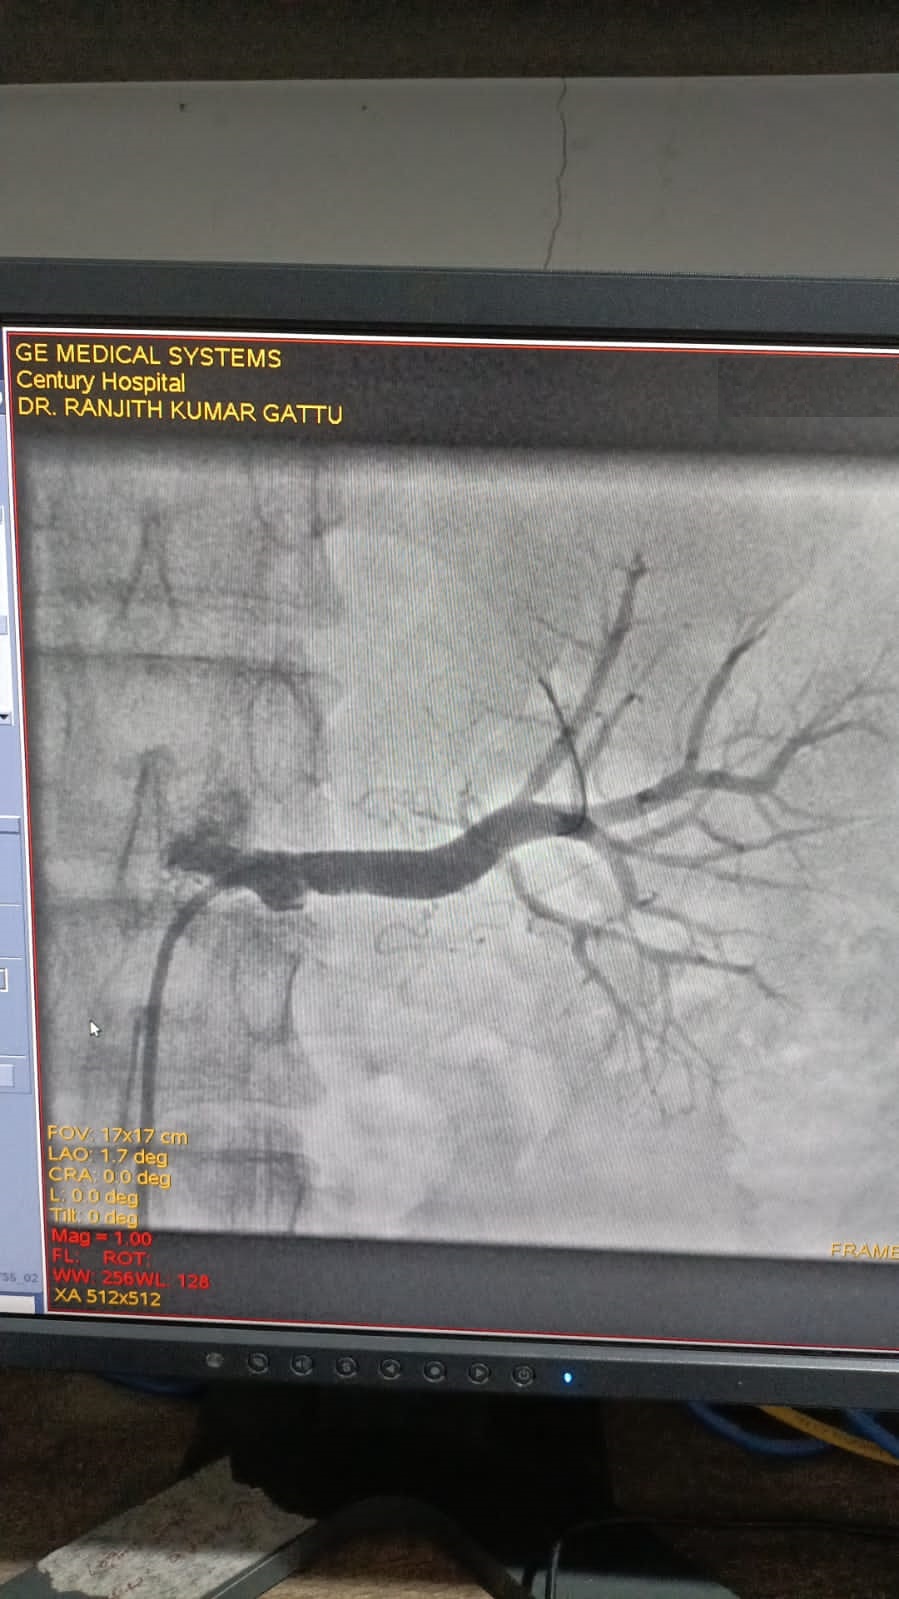

Left Coronary Artery